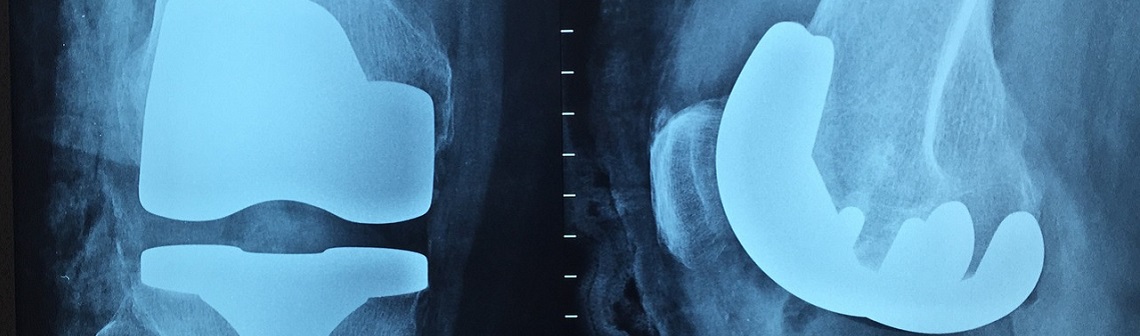

Remplacer une hanche ou un genou par un implant métallique est devenu une opération courante, qui se déroule quotidiennement partout dans le monde. La colonisation bactérienne est l’une des principales causes d’échec de telles chirurgies. Il existe bien des antibiotiques, mais leur administration n’est pas efficace à tous les coups. Ainsi, près de 7 % des cas finissent par une seconde opération, d’extraction cette fois. D’abord de l’implant… et parfois du membre colonisé. Des chercheurs de la Washington State University menés par le professeur Amit Bandyopadhyay, ont voulu mettre au goût du jour les implants en titane développés il y a plus de 50 ans. Leur idée : y ajouter du tantale et du cuivre pour améliorer leur biocompatibilité et contrer du même coup la résistance bactérienne.

Les implants actuels sont composés de Ti6Al4V, un alliage titane-aluminium-vanadium. Amit Bandyopadhyay et son équipe ont fabriqué additivement leur propre alliage par la technique de fusion laser sur lit de poudre. Ce procédé couche par couche consiste à faire fusionner de la poudre au passage d’un laser. Ici, les scientifiques ont mêlé dans des proportions massiques équivalentes du CpTi (plus de 99 % de titane) et du Ti6Al4V pour former du Ti3Al2V. Ils ont ensuite cherché à évaluer les propriétés biologiques et mécaniques de leur nouveau matériau, enrichi de tantale et de cuivre. D’abord, ils lui ont additionné 3 % de cuivre (Cu) et l’ont mis en contact pendant 48 heures avec des lignées bactériennes de bacille pyocyanique (Pseudomonas aeruginosa) et de staphylocoque doré (Staphylococcus aureus). Le cuivre a permis une nette réduction des colonies de bactéries, de 78-86 % comparé au CpTi. L’ajout de 10 % de tantale (Ta) a quant à lui montré une bien meilleure biocompatibilité que le Ti6Al4V, avec une formation osseuse 3,5 fois plus importante ! Enfin, l’alliage complet (Ti3Al2V-10Ta-3Cu) a répondu excellemment aux différents tests de résistance à la fatigue et au cisaillement.